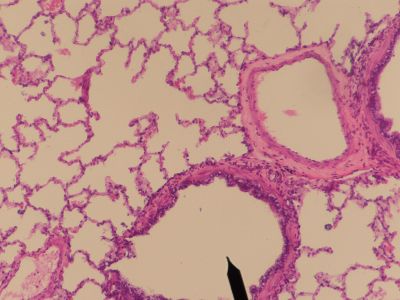

Lung - histology slide

This is a histology slide of lung. The pointer is on a bronchus.

Image by Jpogi at English Wikipedia, via Wikimedia Commons. Public domain.

No changes were made to the original image downloaded (note: this version was downloaded at reduced resolution from Wikimedia Commons).